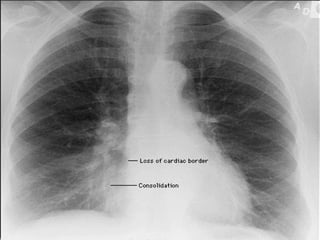

ATELECTASIS No ventilation to lobe beyond the obstruction   Trapped  air absorbed by pulmonary circulation   Segmental/lobar density Compensatory hyper-inflation of normal lungs.